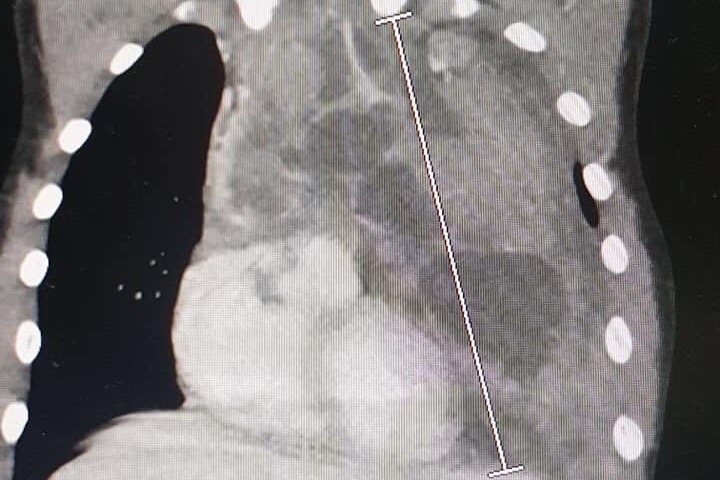

Reese has coughed on and off for nearly a year, while occasionally being short of breath as well. He also complained of pain in his chest area. The symptoms all seemed to point to asthma. On Sunday, January 19, Brandy noticed Reese’s L shoulder being a lot higher than the R, and his L chest area being quite a bit

larger than the R. The ribs on the L side were also sticking out. On Monday they went to the doctor in Brownwood. The nurse practitioner felt like it was inflammation to the sternum from coughing, but Brandy insisted they do a chest x-ray anyway. X-rays don't show as much, but it looked as if he had an enlarged heart. They were advised at 3ish to go to Cooks ER that day. After repeat chest x-rays and a CAT scan at Cooks, they knew they were dealing with a very large mass of lymph nodes compacted into 1 large tumor called a mediastinal tumor. The tumor is pushing his heart to the side and compressing his airway nearly shut. It stretches from the clavicle to the lower rib cage. He was not able to be sedated for procedures due to fear of his airway collapsing. He was a champ during his needle biopsy to the neck lymph node, his R arm PICC line, and the bone marrow aspiration. He was super scared but was the sweetest during the procedures. While all of the results aren’t in, the doctor feels that his cancer is Hodgkins Lymphoma. Reese has a long road ahead, but this cancer is very beatable.Brandy also had Hodgkins disease 20 years ago when she was 19. What better person to guide Reese through the tough times ahead?